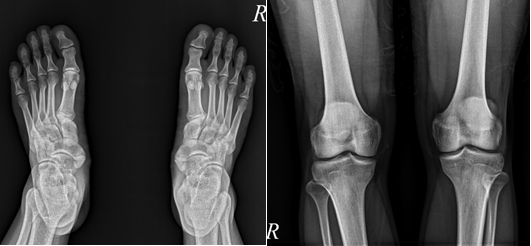

A 23-year-old soldier visit Outpatient Department of Rehabilitation of our hospital for the pain in the bottom of his feet. The patient said that once he exercised the feet hurt a lot, and the pain would relieve after rest. He has been troubled by such a situation since high school. Recently, the situation worsened due to intense training in military service. He mentioned that he had been suffering from chronic knee pain for a long time. The knees were burning and looked reddish, causing pain after exercise even now can be felt heat around knee. During physical examination, we found pustulosis on both palms (Figure 1A & 1B) and hyperostosis in the left sternoclavicular joint. Furthermore, the patient also had a little acne on his face. Plain films of the knee and foot/ankle joints did not show abnormality (Figure 2A). Whole body bone scan (WBBS) divulged a boosted uptake of 99mTc-methylene diphosphonate (99mTc-MDP) at the left knee and both foot/ankle joints (Figure 3). Single photon Emission Computed Tomography (SPECT) with Computed Tomography (CT), using the same tracer, revealed precise pathology at the left knee and both foot/ankle joints (Figure 4A & 4B). The initial impression for this patient was SAPHO syndrome together with enthesopathy of left knee, and both foot/ankle joints. Patient was treated with pain killer and rehabilitation modalities, and his painful episodes improved after three months.

Figure 2A The plain films of the knee joints (left panel) and feet (right panel) show negative findings.s.